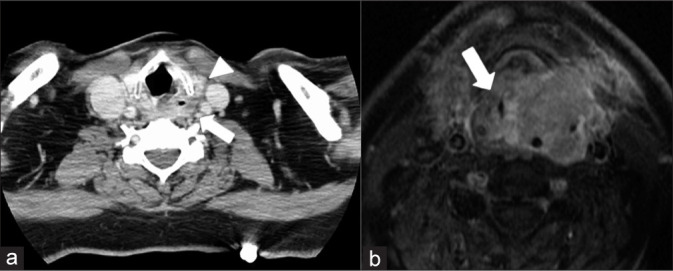

本综述描述了头颈癌(HNCs)急诊病例的放射学表现,包括未确诊和曾接受治疗的患者,重点强调了每次表现的时间紧迫性,以及与相关临床表现和必要治疗的联系,以加强理解和认识。HNC的各种表现将根据其主诉的器官系统来描述。我们将详细介绍每一种疾病的发展和并发症,重点介绍急诊科的临床表现和对诊断至关重要的影像学结果。每个报告将与一个特定的病例一起展示,并展示所获得的精确的计算机断层扫描、磁共振成像、超声或数字减影血管造影图像。病例包括声门肿瘤或转移性颈部淋巴结病引起的气道阻塞;手术并发症血肿或放疗后软组织水肿引起的气道阻塞;肿瘤或淋巴结压迫、颈动脉爆裂、颈动脉狭窄或闭塞等血管并发症;眶间室综合征并发症;骨髓炎和骨放射性坏死的骨科并发症。11例HNC患者与其相关的32张图像。HNC患者在紧急情况下表现出具有挑战性的影像学特征。辨别正确诊断的困难来自复杂的头颈部解剖结构,通常由于出现的晚期和功能状态差而复杂化。放射科医师熟悉常见的HNC急诊表现对于准确诊断和及时治疗至关重要。

This review describes the radiographic findings in emergencies of head and neck cancers (HNCs) in both undiagnosed and previously treated patients, with an emphasis on the temporal urgency of each presentation and in association with the relevant clinical presentation and necessary treatments to enhance understanding and recognition. The various presentations of HNC will be described by the organ system of their presenting complaint. The development and complications of each will be elaborated, with a focus on the clinical presentation in the emergency department and the imaging findings that are critical to recognize in making the diagnosis. Each presentation will be exhibited with a specific patient case and the exact computed tomography, magnetic resonance imaging, ultrasound, or digital subtraction angiography images obtained will be shown. Cases include airway obstruction due to glottic tumor or metastatic cervical lymphadenopathy; airway obstruction due to surgical complications of hematoma, or post-radiation soft-tissue edema; vascular complications of tumor or nodal compression, carotid blowout, carotid stenosis, or occlusion; orbital complications of compartment syndrome; and orthopedic complications of osteomyelitis and osteoradionecrosis. Eleven HNC patient cases are presented with their associated 32 images. HNC patients present with challenging imaging features in the emergent setting. Difficulty in discerning the correct diagnosis arises from the complex head and neck anatomy, often compounded by an advanced stage at presentation and poor functional status. Radiologist familiarity with common HNC emergent presentations is essential for accurate diagnosis and timely treatment.